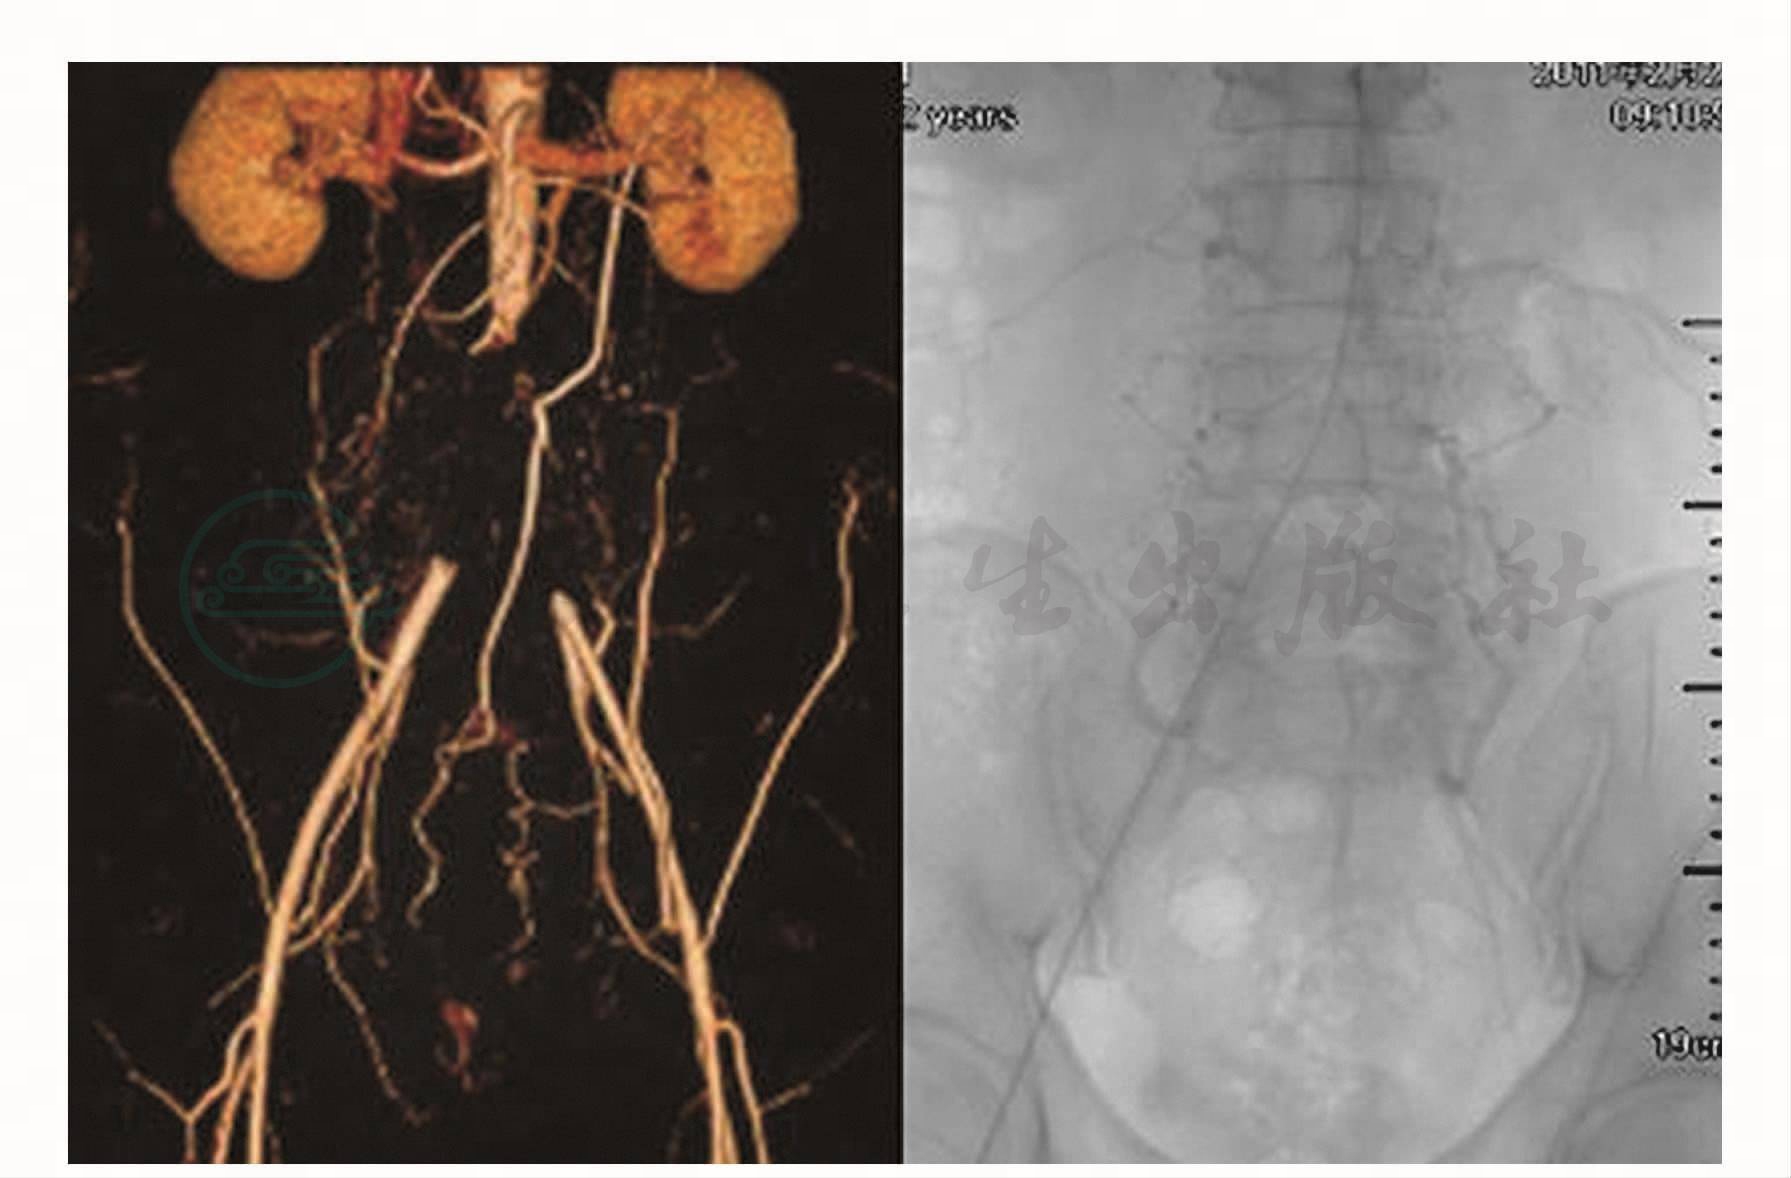

男患,43岁,以“双下肢间歇性跛行半年”为主诉入院。半年前无明显诱因出现双下肢皮温发凉,行走一段距离后出现麻木、乏力、疼痛,休息片刻后缓解。近1个月间歇性跛行症状加重,并出现性功能障碍,由开始性交时臀部、大腿内侧疼痛发展至持续不能勃起。在外院多次住院检查,诊为“椎间盘突出”、“椎管狭窄”、“阳痿”,并进行相应治疗,效果不佳。入院时查体:生命体征平稳,双肺呼吸音清,心音正常。腹平坦,全腹无压痛及反跳痛。双下肢肌肉萎缩,皮肤温度降低,双下肢肌力4级。双侧股动脉搏动明显减弱,足背动脉搏动微弱。CT检查示腹主动脉下段-双侧髂总动脉管腔闭塞,其上方至双侧肾动脉下管腔内散在小块充盈缺损。DSA示腹主动脉下段闭塞,双侧髂总动脉不显影。诊断为主髂动脉闭塞(Leriche综合征),于我科行腔内血管成形术(先经导管溶栓治疗,之后再行对吻式球囊成形及支架置入术),术后患者双下肢皮温改善,双侧股动脉搏动良好,足背动脉可触及,间歇性跛行症状好转(图1)。

图1 CT检查示腹主动脉下段-双侧髂总动脉管腔闭塞; DSA示腹主动脉下段闭塞,双侧髂总动脉不显影